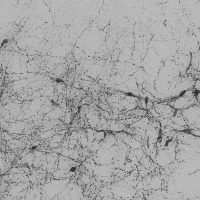

dopamine_th Computer Vision Project

The provided information seems to be insufficient to provide detailed use-cases. The model name, "dopamine_th" implies a possible connection to neurobiology, specifically, to dopamine neurotransmitters. Yet, the "th classes including th" part is unclear, as "th" is not a known term in either computer vision, biology, or bioinformatics domain. It might be a reference to certain classes in your data set, but without further context or clarification, it's challenging to provide accurate use cases. The image of a grey background also doesn't provide significant context. Could you please provide further details concerning this "th" term and more context related to the computer vision model?